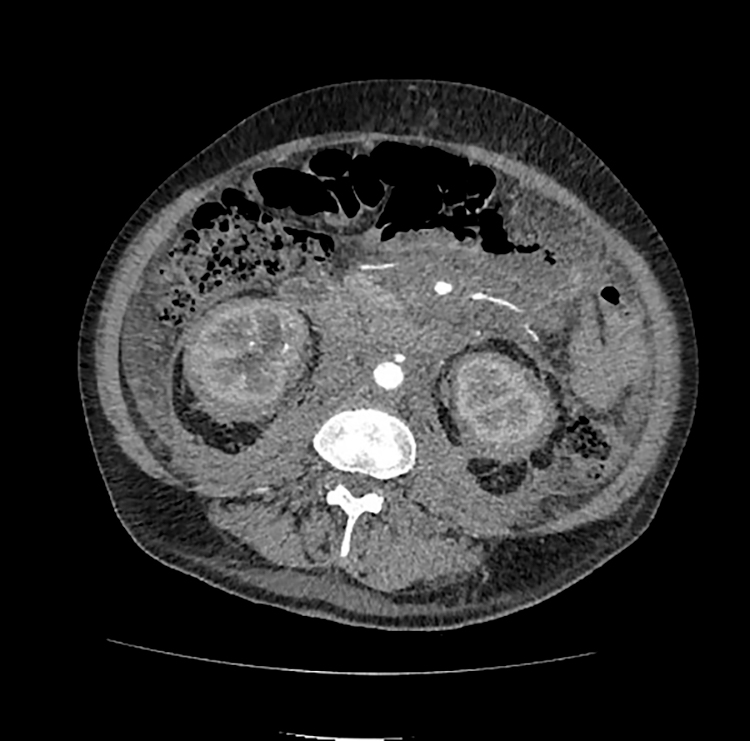

Выявлена дополнительная ткань (инфильтрат? Объем?) забрюшинного пространства с вовлечением парапанкреатической, паранефральной, периуретеральной клетчатки, с распространением вдоль аорты и сосудов брыжейки. Двусторонний гидронефроз, обусловленный компрессией мочеточников и правой лоханки инфильтратом (рисунок 2)

Рис. 2. КТ брюшной полостии забрюшинного пространства, 2023 год

Пациент был выписан на амбулаторный этап наблюдения. Принято решение об инициации терапии вемурафенибом 240 мг х 2 раза в день внутрь. С 20.10.2023 начата терапия. Пациент по данным Единой Электронной Медицинской карты продолжает амбулаторно прием вемурафениба на протяжении более года. Исходя из осмотров гематолога — явления дыхательной недостаточности не беспокоят. Эпизодов гипертермии нет. Выполнялись контрольные КТ ОГК и ОБП с контрастным усилением на фоне проводимой терапии —картина нелангергансоклеточного гистиоцитоза (болезнь Erdheim-Chester), положительная динамика на фоне лечения, с уменьшением выраженности периваскулярной инфильтрации аорты и ее ветвей, уменьшением инфильтрации забрюшинного пространства. Регресс признаков хронического экссудативного перикардита. Уменьшение (нормализация) размеров почек, двусторонний гидронефроз, обусловленный компрессией мочеточников и правой лоханки инфильтратом. Нефростомические дренажи с обеих сторон. Регресс перипортального отека (см. рис. 4-6).

Рис. 5. Утолщение паранефральных перегородок с обеих сторон по типу «волосатых» почек (“hairy” kidney). Слева 2025 год, справа 2023 год. Аксиальная проекция.

Рис. 6. Инфильтрация забрюшинной клетчатки, положительная динамика. Слева 2025 год, справа 2023 год. Аксиальная проекция.